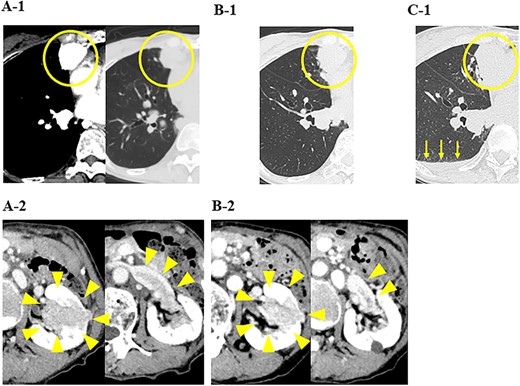

In our hospital, CT-guided core needle biopsy was performed on the pulmonary mass of the right middle lobe. At the time of biopsy, which was performed ~1 month after the last CT scan, increases in the sizes of the pulmonary tumors (tumor growth rate of pulmonary tumors; 29%) (Fig. 1C-1) and pleural effusion (Fig. 1B-1) were noted on CT. A pathological examination revealed that the tumor formed a papillary structure and the lumen was filled with colloids. Since immunohistochemistry results were positive for Tg (Fig. 2), the mass was considered to be pulmonary metastasis of PTC. The patient was diagnosed with pulmonary metastases of PTC, and the administration of lenvatinib was initiated. Since nivolumab and ipilimumab were administered until just before the initiation of lenvatinib, the starting dose of lenvatinib was 8 mg/day. Fatigue (grade 2) and skin disorders (grade 2) developed 3 weeks after the initiation of lenvatinib, and thus, the dose was reduced to 4 mg/day. Three weeks after the dose reduction, hypertension (grade 2) was observed. The patient was administered olmesartan medoxomil, which returned blood pressure to normal.

A pathological examination of the pulmonary mass; (A) tumor cells formed a papillary structure, and the lumen was filled with colloids (H. E. stain), and (B) immunohistochemistry results were positive for Tg.